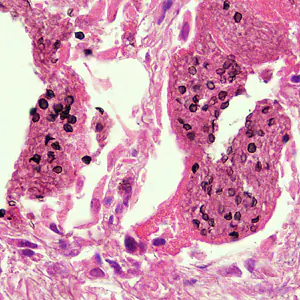

A 49-year-old man with AIDS was admitted to the hospital for complaints of a persisting fever and dry cough. A chest radiograph showed bilateral infiltrate. A sputum specimen was collected and stained with Giemsa, but no parasites were observed. A lung biopsy was obtained, sectioned, and stained with both methenamine silver and hematoxylin and eosin (H&E) stains. Figures A and B show what was observed at 500x magnification on one of the stained sections. What is your diagnosis? Based on what criteria?

Figure A